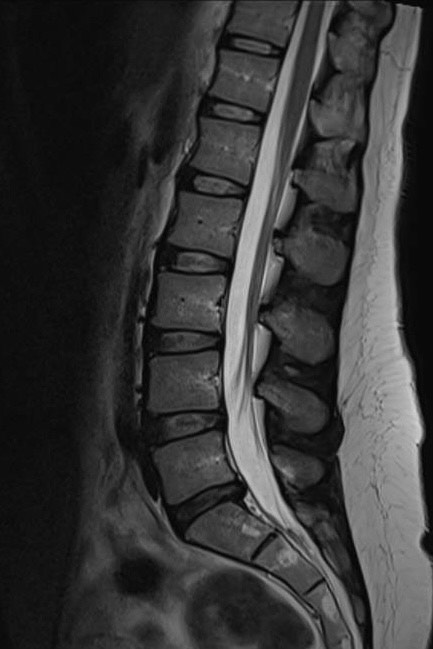

The MRI is just a still life photograph showing structural changes to the area. Some of those findings you are better off not knowing. They can be completely incidental and not linked to your symptoms. Our bodies move and work in a very functional way. The MRI misses this in it’s still life assessment. It is actually taken whilst you are lying down. Missing the weight bearing element that gravity will create. Interestingly there are some new MRI facilities that have now started doing standing MRIs. This would be better in assessing most spinal complaints with the disc compression changing when upright.

A huge study was done on numerous people that did NOT have pain. They were given an MRI on their spine to see the features that were present. The results are amazing and very reassuring that you should be able to return to a pain free life, even if you have a symptomatic version of these findings!

A number of findings are presented in a table above, but lets talk about the “problem” that most of you will be familiar with, a disc bulge. The research showed that the chances of you having a disc bulge in your 30s is 30%. Remember this is in individuals who do not have any pain! As we get older, the rate of this finding increases dramatically. When you are in your 70s, the chances increase to 77%! 77% of people WITHOUT back pain have disc bulges when they are 70. If that statement doesn’t normalise the presence of disc bulges, I don’t know what does. Obviously the pain that can come with them is a different matter, but if you’ve been diagnosed with a disc bulge, I really don’t want you to think you are doomed to a lifetime of pain!